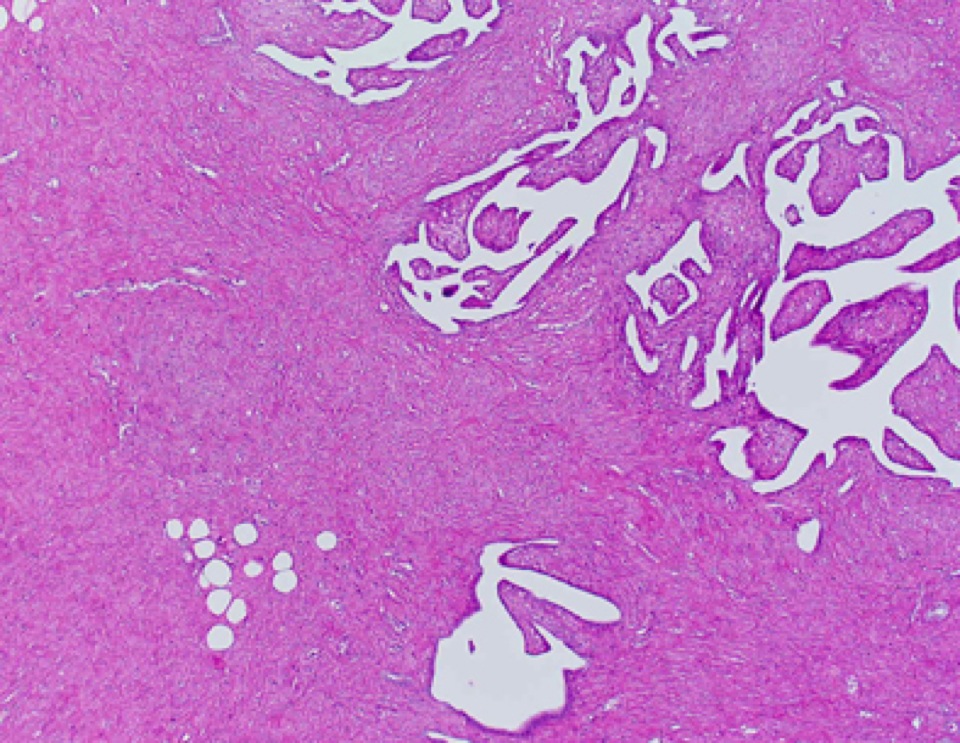

【現病歴】受診の1ヶ月前より発熱・悪寒・咳嗽症状あり。近医を受診し胸部レントゲンにて肺炎を指摘され入院。CT にて左気管支内の腫瘍を疑われ気管支鏡検査を目的に当院呼吸器科紹介外来受診。気管支鏡検査にて左 B10-9入口部に乳頭状の隆起性病変を認め生検施行。病理組織学的に悪性腫瘍性病変と診断された。全身検索では他の部位に腫瘍性病変は確認できず。初診 より1ヶ月後、左肺下葉切除術が施行された。手術材料では気管支入口部を巻き込む形で大きさ 2×1.8×1.5 cm の光沢を持った白色均質充実性病変が認められた。手術材料から作成した腫瘍病変部 HE 標本を配布する。

写真